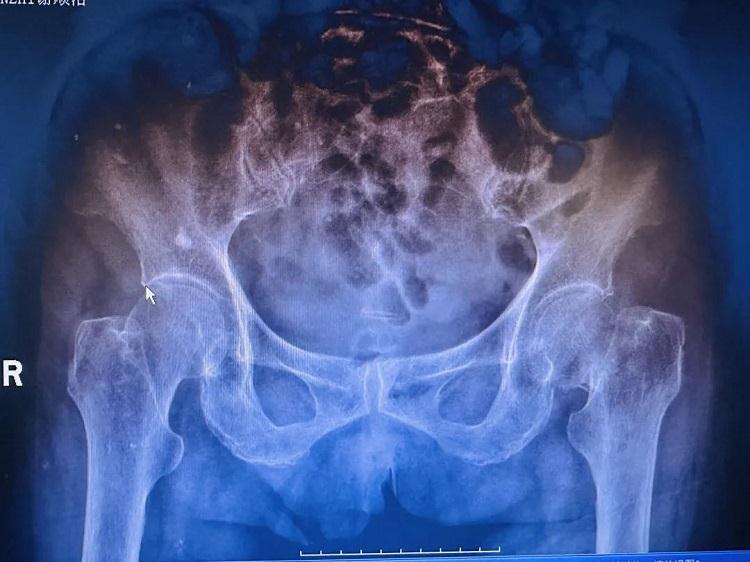

經(jīng)介紹,謝奶奶來到我院就診。接診醫(yī)生楊晟興主治醫(yī)師仔細(xì)查看了謝奶奶的檢查報告及影像資料,明確了患者骨折的類型,并全面評估了患者身體狀況。

出院時,謝奶奶精神矍鑠,髖部切口愈合良好,復(fù)查X線顯示人工股骨頭位置正常。醫(yī)護(hù)人員再三叮囑其出院后要繼續(xù)加強(qiáng)康復(fù)訓(xùn)練,逐步增加活動量,定期復(fù)查,同時做好居家防跌倒措施,加強(qiáng)營養(yǎng)補(bǔ)充。此次手術(shù)成功,打破“高齡=手術(shù)禁區(qū)”固有觀念,為高齡骨折患者的治療帶來了新的希望,展現(xiàn)出我院多學(xué)科協(xié)作的綜合救治實(shí)力,更體現(xiàn)了醫(yī)療團(tuán)隊(duì)對生命的敬畏與專業(yè)堅(jiān)守。